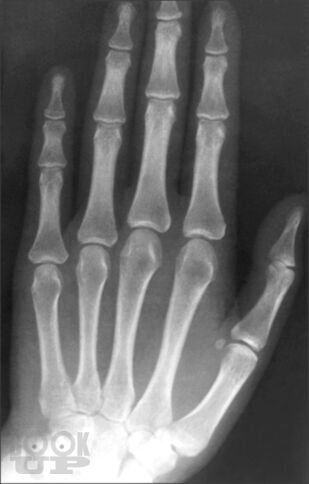

В руководстве изложены общие аспекты артрологии (строение и функция суставов, классификация основных заболеваний суставов, методы диагностики и терапии заболеваний суставов, оценка нарушения функции суставов), особенности клиники, ди агностики, дифференциальной диагностики наиболее частой костносуставной патологии — остеопороза, остеоартроза, ревматоидного артрита, анкилозирующего спондилоартрита, псориатического артрита, подагры, паранеопластического артрита и поражений околосуставного аппарата. В книге отражены особенности суставной патологии в пожилом возрасте.